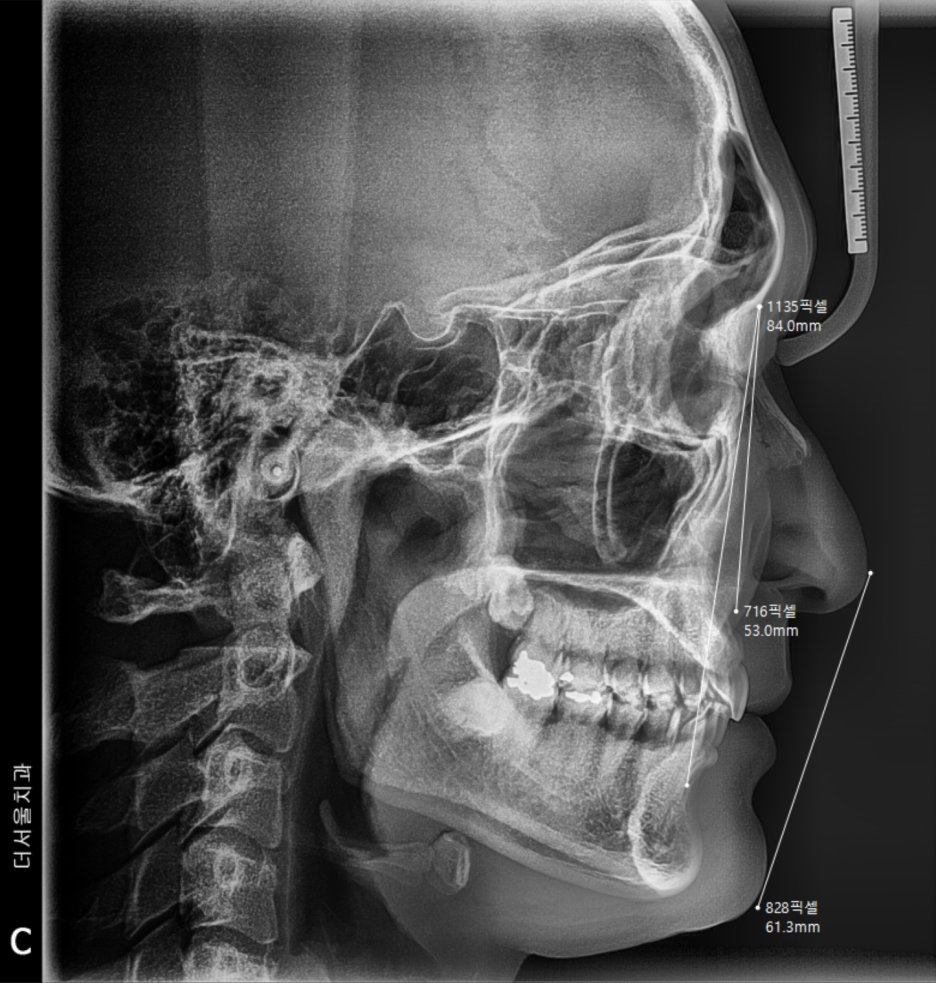

측면에서도 마찬가지로 엑스레이를 찍습니다.

돌출입 또는 무턱의 정도를 알 수 있으며,

코 끝과 턱 끝을 이은 심미선(리케츠라인)을

활용 해서 환자를 어떤 방향으로 끌고 가야

되는지를 알려줄 수 있는 정보입니다.